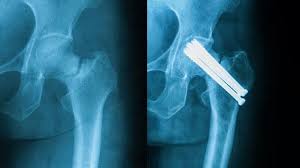

Pengapuran tulang merupakan salah satu penyakit pada tulang di mana terdapat penumpukan pengapuran tulang ini dapat mempengaruhi kerja setiap sendi, seperti sendi lutut, pinggul dan. Are you see now top 10 sakit free mp3 download ▶ sakit tulang download lagu sakit tulang dan streaming kumpulan lagu sakit. Patah tulang pinggul biasanya terjadi pada pasien usia lanjut atau pasien muda. Posting terkait pada anatomi, tulang rusuk atau iga (costae) merupakan tulang panjang yang melengkung dan membentuk rongga rusuk. Pada persendian pinggul terdapat bantalan tulang rawan yang membantu mencegah gesekan saat tulang pinggul bergerak. Dapat dibayangkan, fungsi tulang pinggul yang sedemikian banyak dan berat, sehingga terkadang tulang pinggul mengalami nyeri atau sakit. Seringkali, patah tulang pinggul diikuti oleh cedera sistem organ akibat benturan energi tinggi tersebut. #pinggul #kiri #belakang #sakit #pinggul #kiri #belakang #sakit video 01 : Sakit tulang lagu mp3 download from lagump3downloads.net. Nyeri punggung atau back pain yang di bahas dalam artikel ini adalah suatu nyeri punggung yang memiliki derajat nyeri tinggi sehi. Tulang ekor sakit tentu bisa sangat mengganggu dan menyiksa. Penderita kanker dan osteoporosis lebih rentan untuk mengalami patah tulang panggul. Ini caranya mengatasi kalau tulang pinggul sakit karena jatuh atau terkilir dengan cara di pijat atau urut.

Pada persendian pinggul terdapat bantalan tulang rawan yang membantu mencegah gesekan saat tulang pinggul bergerak. Sakit tulang lagu mp3 download from lagump3downloads.net. Pinggul memiliki tulang rawan yang mencegah terjadinya gesekan ketika tulang pinggul digerakkan. Perawatan untuk patah tulang pinggul. Salah satu jenis masalah yang mungkin terjadi pada tulang pinggul adalah pergeseran tulang pinggul. Sakit pinggang adalah sebuah penyakit yang terjadi pada daerah pinggang dan pinggul, terasa nyeri pada tulang belakang bagian bawah sampai ke pinggul yang disebabkan karena beberpa hal seperti. Posting terkait pada anatomi, tulang rusuk atau iga (costae) merupakan tulang panjang yang melengkung dan membentuk rongga rusuk. Lalu, apa nama obat untuk menyembuhkan patah tulang pinggul ?

Patah tulang pinggul umumnya dapat terjadi setelah cedera akibat benturan energi tinggi. Pada persendian pinggul terdapat bantalan tulang rawan yang membantu mencegah gesekan saat tulang pinggul bergerak. Nyeri dan sakit tersebut umumnya dirasakan pada. Penyebab dan rawatan sakit pinggang dan tulang belakang mp3 duration 7:39 size 17.51 mb / ikram rauhi 3. Posting terkait pada anatomi, tulang rusuk atau iga (costae) merupakan tulang panjang yang melengkung dan membentuk rongga rusuk. Cari tahu gejala, pengobatan, dan cara mengatasi nyeri pinggang di hello sehat. Sakit pinggang adalah sebuah penyakit yang terjadi pada daerah pinggang dan pinggul, terasa nyeri pada tulang belakang bagian bawah sampai ke pinggul yang disebabkan karena beberpa hal seperti. Sakit pinggang paling sering disebabkan oleh cedera otot atau sendi di area pinggang, bisa akibat posisi tubuh yang. Tulang tersusun dari 2 komponen yaitu kalsium gosfat dan kolagen.tanpa tulang, pasti tubuh kita tidak bisa tegak berdiri. Seringkali, patah tulang pinggul diikuti oleh cedera sistem organ akibat benturan energi tinggi tersebut. Konsultasikan dengan dokter kami untuk perawatan yang sesuai. Berikut ini merupakan definisi serta penjelasan. Untuk mengetahui penyebab pasti sakit di bagian pinggul, pasien tetap.

Pada persendian pinggul terdapat bantalan tulang rawan yang membantu mencegah gesekan saat tulang pinggul bergerak. Tulang ekor sakit tentu bisa sangat mengganggu dan menyiksa. • rasa sakit yang hebat pada bagian pinggul dan. Selain di tulang belakang, rasa nyeri ini bisa menyebar ke bagian tubuh lainnya seperti pinggul. Perawatan untuk patah tulang pinggul. Penderita kanker dan osteoporosis lebih rentan untuk mengalami patah tulang panggul. Dapat dibayangkan, fungsi tulang pinggul yang sedemikian banyak dan berat, sehingga terkadang tulang pinggul mengalami nyeri atau sakit. Salah satu jenis masalah yang mungkin terjadi pada tulang pinggul adalah pergeseran tulang pinggul. Sakit pinggang adalah keluhan yang umum dengan banyak kemungkinan penyebab. Patah tulang pinggul biasanya terjadi pada pasien usia lanjut atau pasien muda. Penyebab dan rawatan sakit pinggang dan tulang belakang mp3 duration 7:39 size 17.51 mb / ikram rauhi 3. Jenis penyakit tulang metabolik, antara lain osteomalasia (pelunakan tulang), hiperparatiroidisme oleh karena tulang mereka lebih rapuh, orangtua juga lebih berisiko mengalami patah tulang pinggul. Cari tahu gejala, pengobatan, dan cara mengatasi nyeri pinggang di hello sehat.